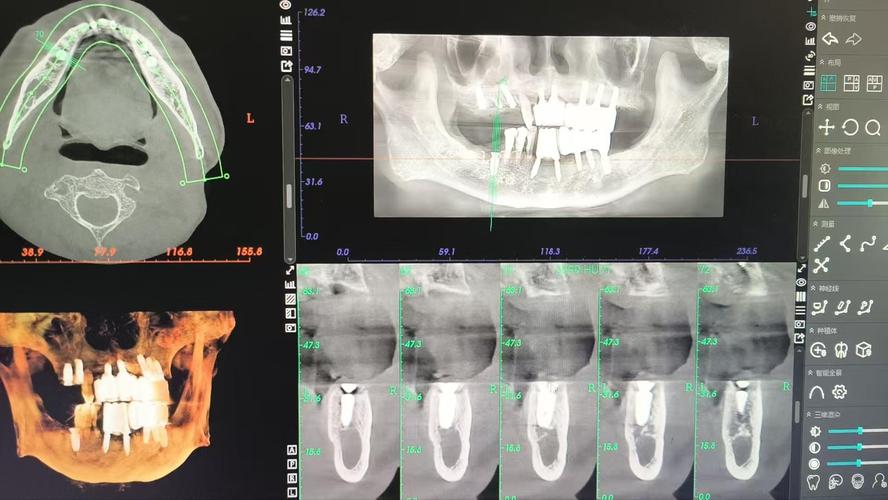

种植体植入后1周内属于早期恢复阶段,此时患者可能存在术后肿胀、疼痛等反应,CT检查并非常规操作,但在特定情况下需紧急进行,若术后出现剧烈疼痛、咬合异常或怀疑种植体移位、穿入上颌窦、下牙槽神经等情况,CT(尤其是锥形束CT,CBCT)可清晰显示种植体在颌骨内的位置、方向以及与重要解剖结构(如神经管、窦腔)的关系,帮助医生判断是否需要调整或处理并发症,此阶段若需CT检查,通常以低剂量、快速扫描为原则,减少辐射暴露。

种植体与颌骨形成骨结合是种植成功的关键,这一阶段(通常为3个月,上颌骨可能需4-6个月)的随访检查尤为重要,临床医生常通过临床检查(如叩诊、松动度评估)结合影像学检查判断骨结合情况,此时若患者无明显症状,常规口腔曲面断层片(OPT)可能已足够,但对于骨结合情况复杂、存在骨缺损或需要精确评估骨整合程度的病例,CBCT是更优选择,CBCT能三维显示种植体周围骨小梁的结构、密度以及种植体与骨界面的接触情况,判断骨结合是否良好,为负重时机提供依据,对于骨质疏松患者或骨量不足需植骨的病例,CBCT可清晰显示植骨材料的吸收与新生骨的形成情况。

在口腔种植领域,CBCT是首选的影像学检查方式,相较于普通CT,CBCT具有辐射剂量更低(仅为普通CT的1/10-1/100)、扫描时间短(几秒至几十秒)、空间分辨率高、能三维重建等优势,可清晰显示种植体、牙槽骨、邻牙、神经管、上颌窦等精细结构,且费用相对较低,普通CT(如螺旋CT)则适用于需要评估种植体与颌骨整体关系,或怀疑种植体穿入颌骨深层组织(如翼腭窝)等复杂情况,但其辐射剂量较高,一般不作为常规检查。

种植体为金属材质,可能在CT成像时产生“金属伪影”,影响周围组织的观察,但近年来,CBCT设备已配备金属伪影校正算法(如MAR技术),可有效减少伪影干扰,清晰显示种植体周围骨组织和硬骨板的完整性,确保诊断准确性。